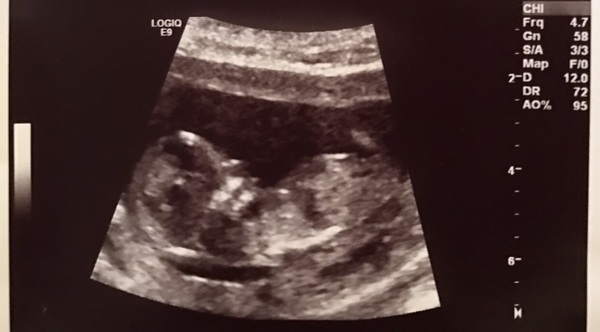

But has managed to book me an early scan on Thursday, which is great news. My NT scan is at 12 weeks, and I didn't really want to wait another 2 weeks worrying that there would be something wrong. So all being well (and I feel like all is well) we'll just get a sneak preview of our bean!